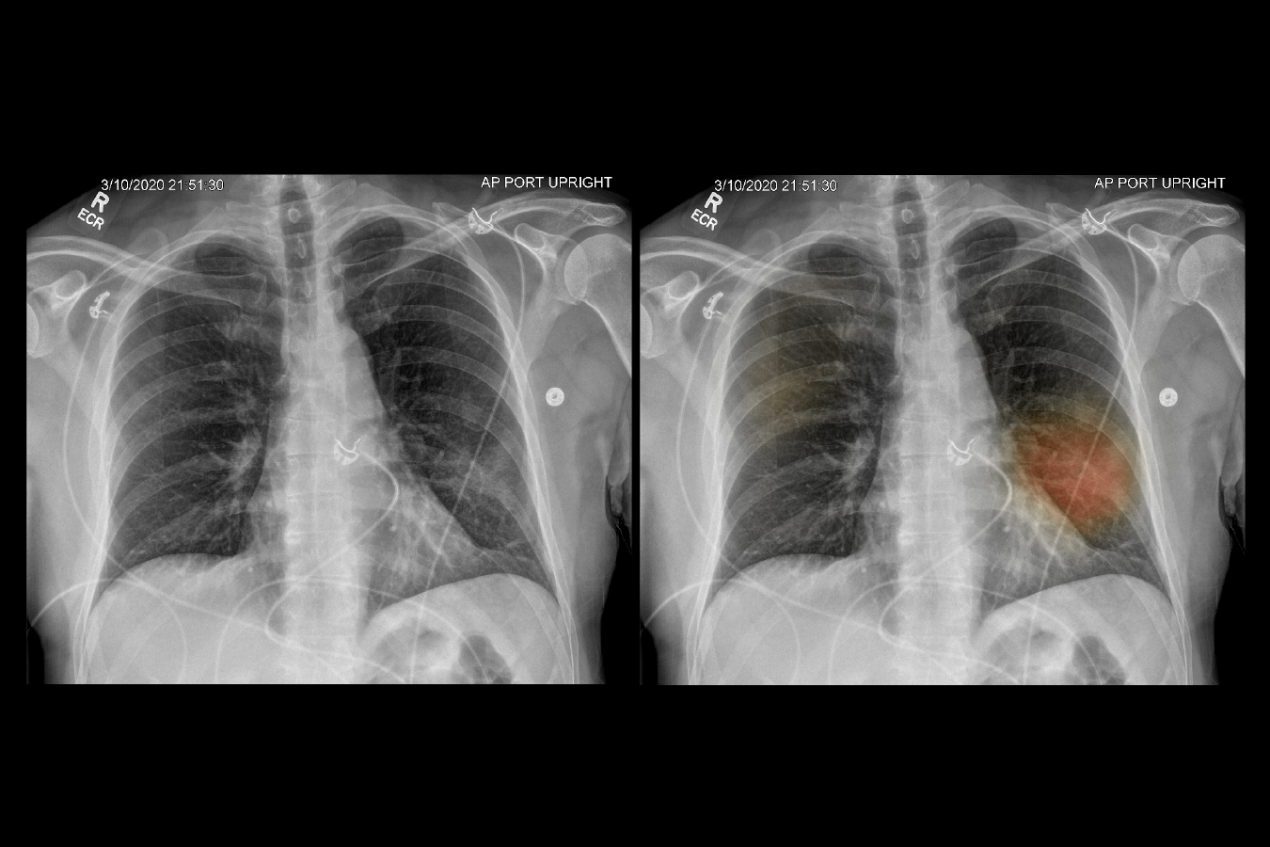

En este artículo, proponen una técnica novedosa llamada Detector rápido de COVID-19 (FCOD) para tener una detección rápida de COVID-19 mediante imágenes de rayos X, con el uso de deep learning.

Para evaluar el FCOD, utilizaron covid-chestxray-dataset, que contiene 940 imágenes típicas de rayos X de tórax disponibles públicamente. Los resultados muestran que el FCOD puede proporcionar precisión, puntuación F1 y AUC del 96%, 96% y 0,95%, respectivamente, al clasificar COVID-19 durante 0,014 s para cada caso.

Su investigación parte de la idea de que la imagen radiológica ayuda a diferenciar con gran precisión una neumonía provocada por coronavirus de otra causada por patógenos diferentes.

Cuando un paciente llega al departamento de urgencias con síntomas sospechosos de COVID-19, los médicos solicitan una radiografía de tórax como parte del protocolo estándar. El algoritmo evalúa automáticamente la radiografía tan pronto como se toma la imagen.